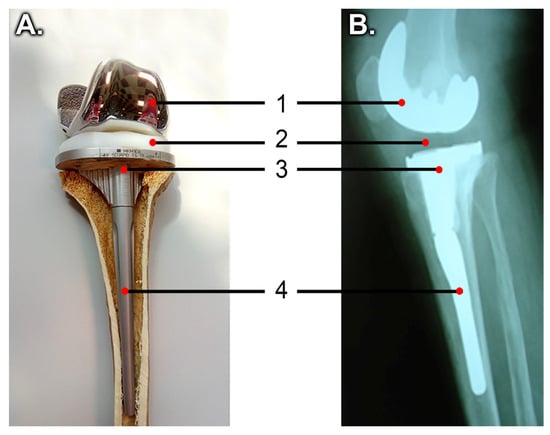

| Tibial component | 4428 | 104,800 | 0.31 |

| Tibial extension | 4428 | 104,800 | 0.31 |